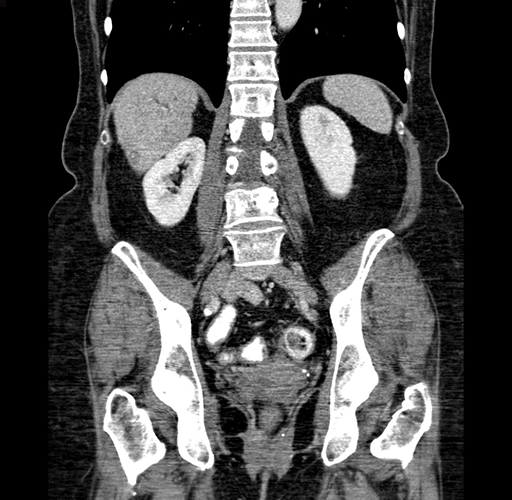

Pre-Chemo: Coronal Venous

Coronal Venous